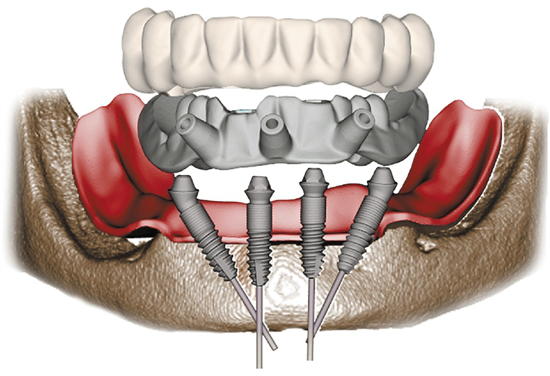

海涛口腔种植科主任表示患者完全不必担忧,种植牙技术是海涛口腔的特色技术,此次推出的原装进口种植牙采用的海涛口腔的数字化导航种牙技术,该技术通过CBCT获取缺牙患者的口腔信息,在计算机的辅助下准确地将需要种植的数量、种植的位置、角度和深度进行分析,制作好种植手术导板,手术时口腔医生在根据导板划定的位置准确植入种植体,微创无痛,减少了感染的风险,提高手术的安全性。由于其植入精准度高,使得种植手术疗程也大大缩短。正是该技术的独特优势,使得原装进口种植牙历经三年依然热度不减,受到众多缺牙患者的追捧。